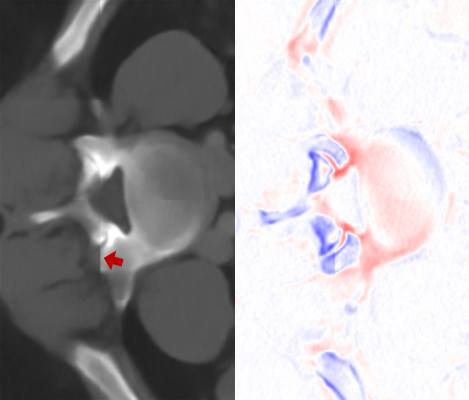

Figure 7: Visual comparisons of different methods against SAINT. The difference maps are provided to the right of the results for better visualization. Images are best viewed when magnified.

In this section, we evaluate the performance of our method and other SISR approaches. Quantitative comparisons are presented in Table 2. MDCSRN uses a DenseNet structure with batch normalization, which has been shown to adversely affect performance in super-resolution tasks [17, 27]. Furthermore, inference with 3D patches lead to observable artifacts where the patches are stitched together, as shown in the mDCSRN results in Fig. 7.

For liver, colon and hepatic vessels datasets, SAINT drastically outperforms the competing methods; however, the increase in performance is less significant with the kidney dataset. Generalizing over unseen dataset is a challenging problem for all data-driven methods, as factors such as acquisition machines, acquisition parameters, etc. subtly change the data distribution. Furthermore, quantitative measurements such as PSNR and SSIM do not always measure image quality well.

We visually inspect the results and find that SAINT generates richer detail when compared to other methods. It is evident in Fig. 7 that there is a least amount of structural artifacts remaining in the different images produced by SAINT. For more discussion on SAINT’s advantage in resolving the memory bottleneck and more slice interpolation results, please refer to the supplemental material section.